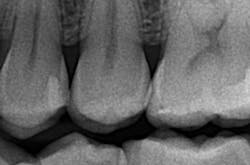

The removal of dental hard tissue is accomplished by what is known as thermomechanical photon-induced water-mediated ablation, which is a process in which the micro-explosive force of photons on water droplets results in the selective removal of carious dentin (figures 2a–2d). The laser energy seeks out tissue with higher water content, such as a carious lesion, and evaporates it without contact, vibration, or the introduction of microfractures, leaving the surrounding healthy enamel and dentin intact.

Figures 2a–2d: A Class II posterior cavity preparation